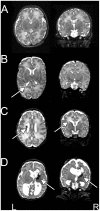

The cerebral white matter is vulnerable to injury in very preterm infants (born prior to 30 weeks gestation), resulting in a spectrum of lesions. These range from severe forms, including cystic periventricular leukomalacia and periventricular hemorrhagic infarction, to minor focal punctate lesions. Moderate to severe white matter injury in preterm infants has been shown to predict later neurodevelopmental disability, although outcomes can vary widely in infants with qualitatively comparable lesions. Resting state functional connectivity magnetic resonance imaging has been increasingly utilized in neurodevelopmental investigations and may provide complementary information regarding the impact of white matter injury on the developing brain. We performed resting state functional connectivity magnetic resonance imaging at term equivalent postmenstrual age in fourteen preterm infants with moderate to severe white matter injury secondary to periventricular hemorrhagic infarction. In these subjects, resting state networks were identifiable throughout the brain. Patterns of aberrant functional connectivity were observed and depended upon injury severity. Comparisons were performed against data obtained from prematurely-born infants with mild white matter injury and healthy, term-born infants and demonstrated group differences. These results reveal structural-functional correlates of preterm white matter injury and carry implications for future investigations of neurodevelopmental disability.